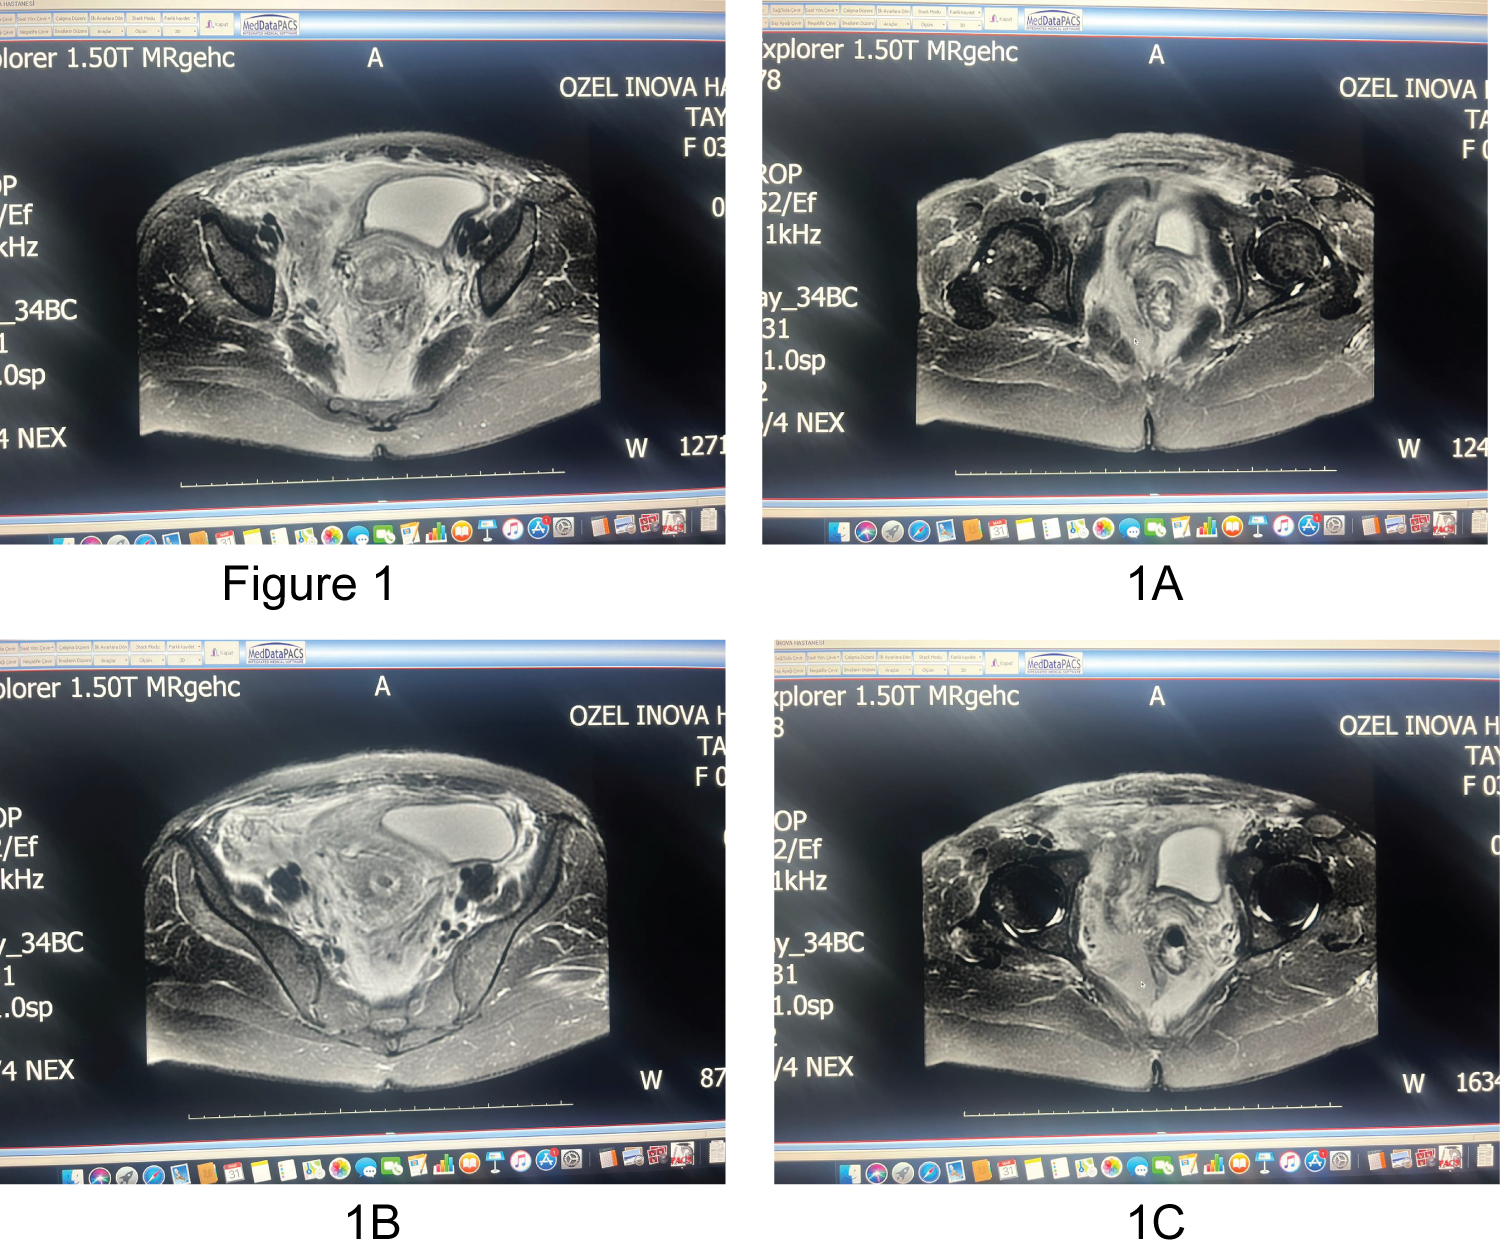

She was cooperative and oriented but in postop 14 hours period, her follow-up Hb level started dropping from 10.4 to 8.6, 6.9 and 6.7 respectively. Most serious complication of VBAC for patient including doctor is uterine rupture. Transvaginal and suprapubic ultrasound was performed to rule out this diagnosis immediately, and USG showed that uterus was intact, and no fluid was found in Douglas pouch. Pelvic MR showed that big (measurements) retroperitoneal fluid was all around the pelvis reaching umbilicus and was squeezing the bladder bilaterally (Figure 1a, Figure 1b and Figure 1c). Patient was stable. Under analgesia her pelvic pain was absent, and her abdominal examinations were normal. Even though patient was stable, 2 nd surgery was considered to manage postpartum hemorrhage. There was a chance that another surgery to patient and surgical evacuation might lead to loss of the advantages of the tamponing effect on the bleeding source which could result in undue dissection and end up with a fatal outcome. So, we decided to follow up the hematoma conservatively with close, careful monitoring. Tersier referral hospital was informed about possible arterial embolization, or another further surgery as needed.

Figure 1: MR showed that big dissemine retroperitoneal fluid was all around the pelvis reaching umbilicus and was squeezing the bladder bilaterally. (a) T1 weighted fat-suppressed transvers MR imaging; (b) T1 weighted fat-suppressed sagittal MR imaging; (c) T2 weighted transvers MR imaging. View Figure 1